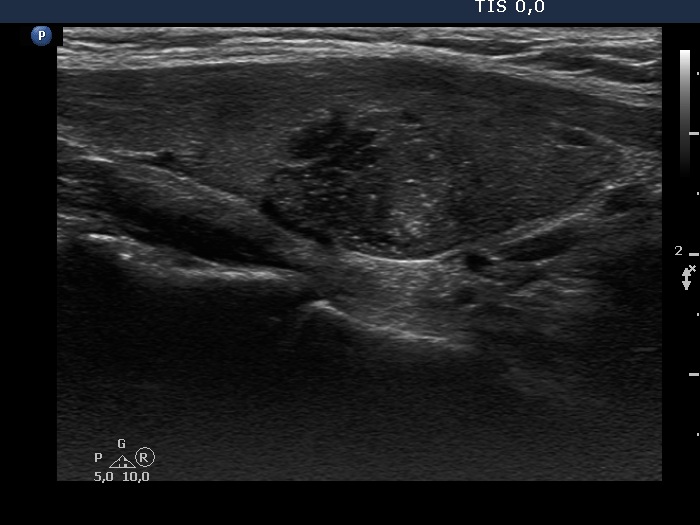

Papillary carcinoma (histological diagnosis) - case conp 035 |

The thyroid presented in the left images is composed of moderately hypoechogenic and hypoechogenic nodules, while the lobe in the malignant case is diffusely hypoechogenic and has a less hypoechogenic but more inhomogeneous lesion in its dorsal part. Both the left thyroid and the malignant nodule in the right images have hyperechogenic granules and lines which correspond to a connective tissue.